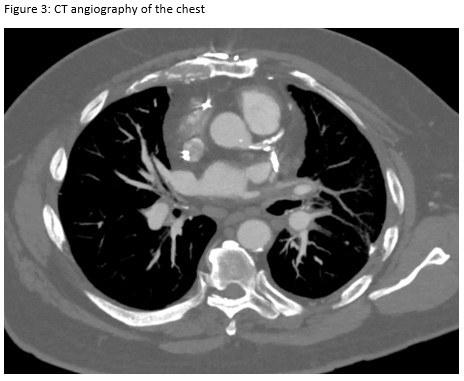

A 72-year-old man presented for evaluation of progressive dyspnea with concern for interstitial lung disease (ILD). He had an extensive cardiac history with prior cardiac bypass surgery and atrial appendage exclusion, followed by multiple subsequent radiofrequency ablations targeting arrhythmogenic foci. His last ablation procedure was three years prior to presentation. He reported reduced exertional tolerance, and was only able to ambulate a few blocks. As a part of his work-up, his local pulmonologist had obtained a high-resolution computed tomography (HRCT) of the chest, which showed abnormalities limited to the left upper lobe (Figure 1). He was treated with antibiotic therapy and corticosteroids but had no improvement so a surgical lung biopsy was performed. These images and biopsies were reviewed at our institution. A representative picture of histology from the biopsy is shown in Figure 2. After his visit to the ILD clinic, a CT angiogram of the chest was obtained and is shown in Figure 3.